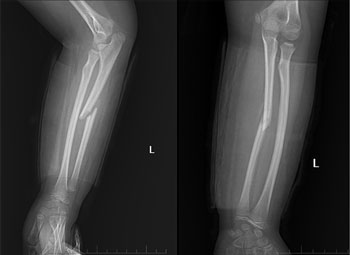

Tại Trung tâm Y tế Lâm Thao, sau khi thăm khám và thực hiện các cận lâm sàng cần thiết, các bác sĩ xác định người bệnh bị gãy 1/3 giữa xương trụ tay trái can lệch, chỉ định phẫu thuật sửa trục chi kết hợp xương bằng nẹp vít khoá cho người bệnh.

Ca phẫu thuật diễn ra thành công, hiện tại người bệnh có sức khỏe và tâm lý ổn định, tình trạng đau nhức đã thuyên giảm nhiều, có thể thực hiện các động tác tập vận động đơn giản theo hướng dẫn.